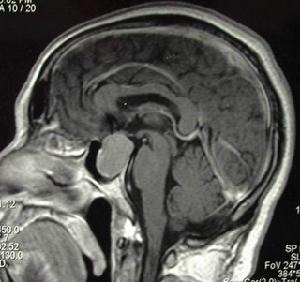

(二)垂體卒中:

主要表現為①突然發生顱壓增高的症狀;

②常有蝶鞍鄰近組織壓迫的症狀,如向上壓迫視覺通路、間腦和中腦,引起視力下降、視野缺損及生命體徵改變;向下壓迫丘腦引起血壓、體溫、呼吸及心律紊亂;壓迫側面進入海綿竇引起眼外肌麻痹、三叉神經症狀及靜脈回流障礙;

③下丘腦-垂體功能減退的症狀。尚有不少垂體卒中患者缺乏原有垂體腺瘤的症狀,因此遇到原因不明的突發顱壓增高,尤其伴視力障礙、眼肌麻痹等壓迫症狀者,應警惕垂體卒中。

蝶鞍擴大可見於下丘腦或垂體腫瘤。微腺瘤蝶鞍無擴大但可有局限性破壞,CT或MRI有助進一步診斷。